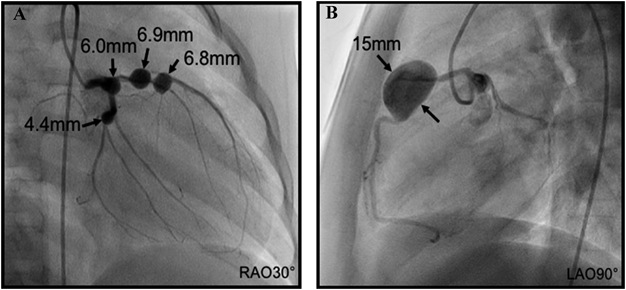

On day 7, echocardiography to detect the origin of fever showed bilateral coronary arterial aneurysms, the appearance of which resembled a string of beads. There was a 5.6-mm (Z 6.7) aneurysm on the left main coronary trunk (LMT), 6.1-mm (Z 7.9) and 5.6-mm (Z 7.3) aneurysms on the left anterior descending artery (LAD), and an 8.3-mm (Z 10.7) aneurysm on the right coronary artery (RCA) (Fig. 1). Therefore, the patient was diagnosed with incomplete KD and we administered IVIG (2 g/kg) and ASA (30 mg/kg/day). Cyclosporine A (6 mg/kg/day) was also given to reduce inflammation. Fever improved 12 hours after the initiation of IVIG, but recurred at 36 hours. No changes were observed in coronary aneurysms. Due to the possibility of the further expansion of coronary aneurysms, the patient was transferred to another hospital for plasma exchange. Plasma exchange was performed for 3 days, which reduced his fever and C-reactive protein level.

Fig. 1 Parasternal short axis view showing three aneurysms on the left coronary artery (A) and one on the right coronary artery (B) with measurements (mm) (arrows)

Ao, aorta.